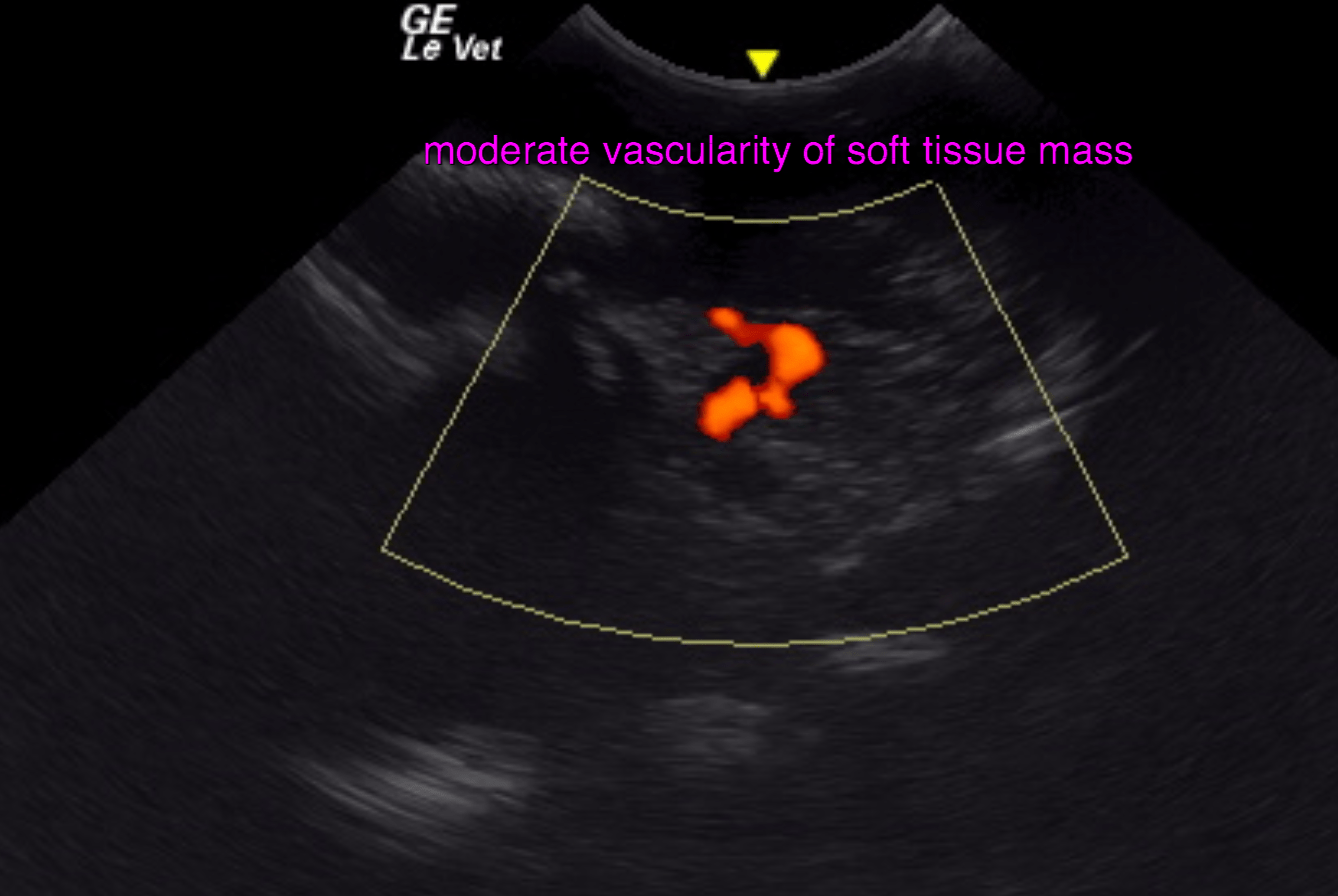

ultrasound of the left maxilla – A large irregular moderately vascularized, cavernous and non-uniformly hypoechoic soft tissue mass is seen perforating the left maxillary bone through an irregularly marginated bony defect. Multifocal amorphous periosteal new bone is seen emerging from the left maxilla and zygomatic arch. Multifocal small permeative lytic defects seem to be present at the rostral margin of the zygomatic arch as well.